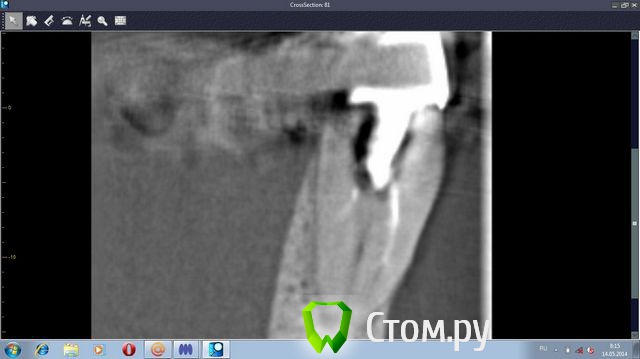

stradalitca Опубликовано 20 мая, 2014 Автор Поделиться Опубликовано 20 мая, 2014 (изменено) Добрый вечер! Я тут ещё глянула как установлен штифт на четвёрке снизу справа. Вот фото в проекциях. Неужели зуб тоже пробит штифтом? или пойдёт ? и я зря переживаю. Изменено 20 мая, 2014 пользователем stradalitca Ссылка на комментарий

Korel Опубликовано 23 мая, 2014 Поделиться Опубликовано 23 мая, 2014 Неужели зуб тоже пробит штифтом? Похоже на то. А Вы не рассматривали для Вашей мамы вариант (на н\чел.) бюгельный протез с замковыми креплениями. 1 Ссылка на комментарий

stradalitca Опубликовано 23 мая, 2014 Автор Поделиться Опубликовано 23 мая, 2014 почитала про мплантанты. Получается, что нам это не особо подходит. Начиная с того, что надо вылечить всю остальную челюсть - то есть убрать очаги воспаления. А воспаление видно невоооружённым глазом. Сегодня у неё стала кровить нижняя четвёрка справа. то ли от полосканий солью, то ли дают знать о себе очередной неудавшийся штифт.А бюгельный протез Вы предлагаете на место моста из 9 коронок и плюс 5,6,7 слева? я правильно поняла? Ссылка на комментарий